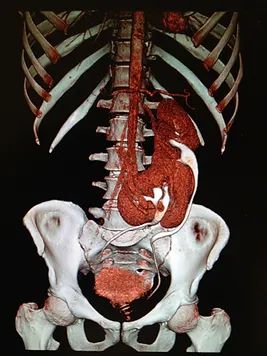

A hormone-secreting tumour that can occur in the adrenal glands. Phaeochromocytomas usually develop in the small glands on top of the kidneys (adrenal glands). They most commonly affect people between the ages of 20 and 50, but can occur at any age. Because of hormones secreted, symptoms include high blood pressure, sweating, rapid heartbeat and headache. Surgery to remove the tumour is usually required.